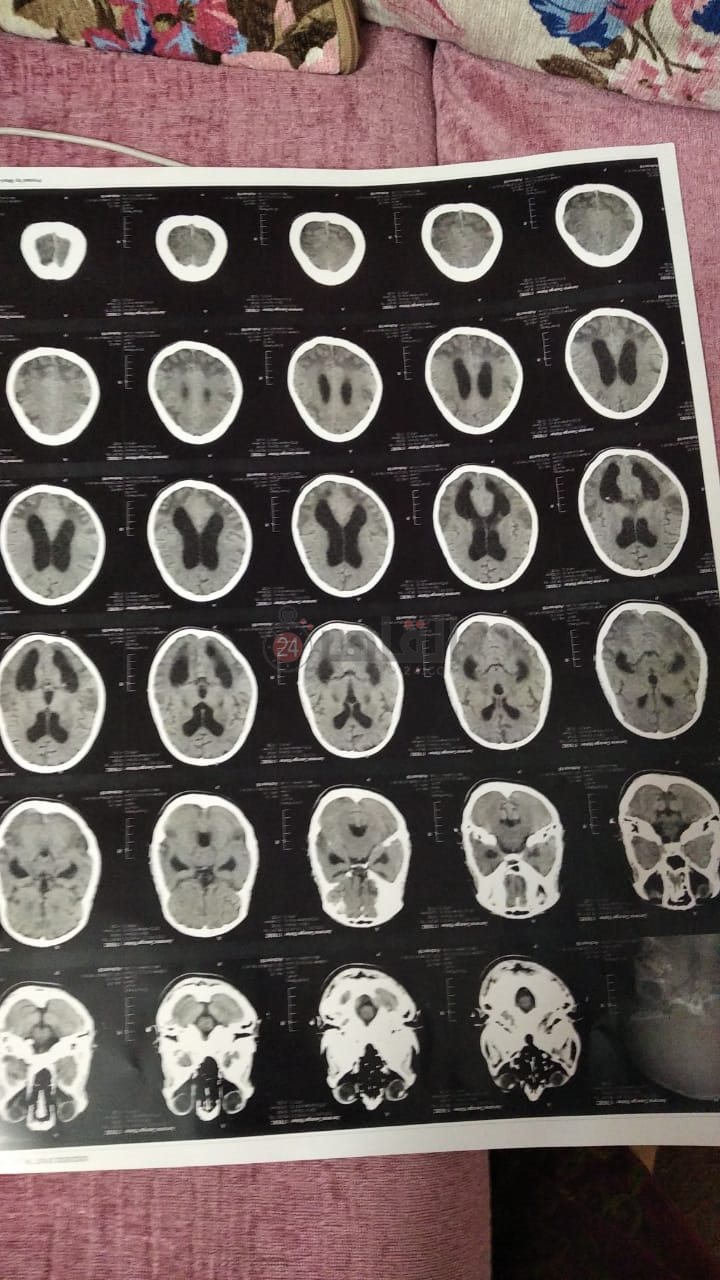

وواصل الأم حديثها: توجهتٌ مؤخرًا إلى طبيب آخر، أكد لي أن المخ حدث به تلف بنسبة 90%، موضحة: قالي خلايا مخها اتبخرت، مخها بقى هواء خلاص.